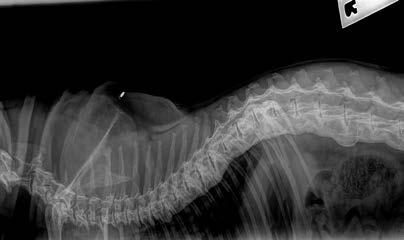

Ultrasonography of the right perineal swelling revealed a fluid-filled object, suspected to be the urinary bladder, herniated through the pelvic diaphragm. Faecal matter was also apparent on ultrasound. Orthogonal survey abdominal radiography was performed. A urethral catheter was placed, and positive contrast cystography performed by instilling 5mL of contrast media (Urografin®; Bayer Australia Ltd, Pymble NSW, 2073, Australia) into the urinary catheter. Repeat orthogonal radiography confirmed urinary bladder retroflexion (Figure 1a). The bladder was then manually reduced into an appropriate anatomical position (Figure 1b). Due to the severity of the deficit, the bladder was unable to remain

Figure 1. Lateral abdominal radiography following positive contrast cystography identifying urinary bladder retroflexion (a). The bladder was then manually reduced into an appropriate anatomical position (b).